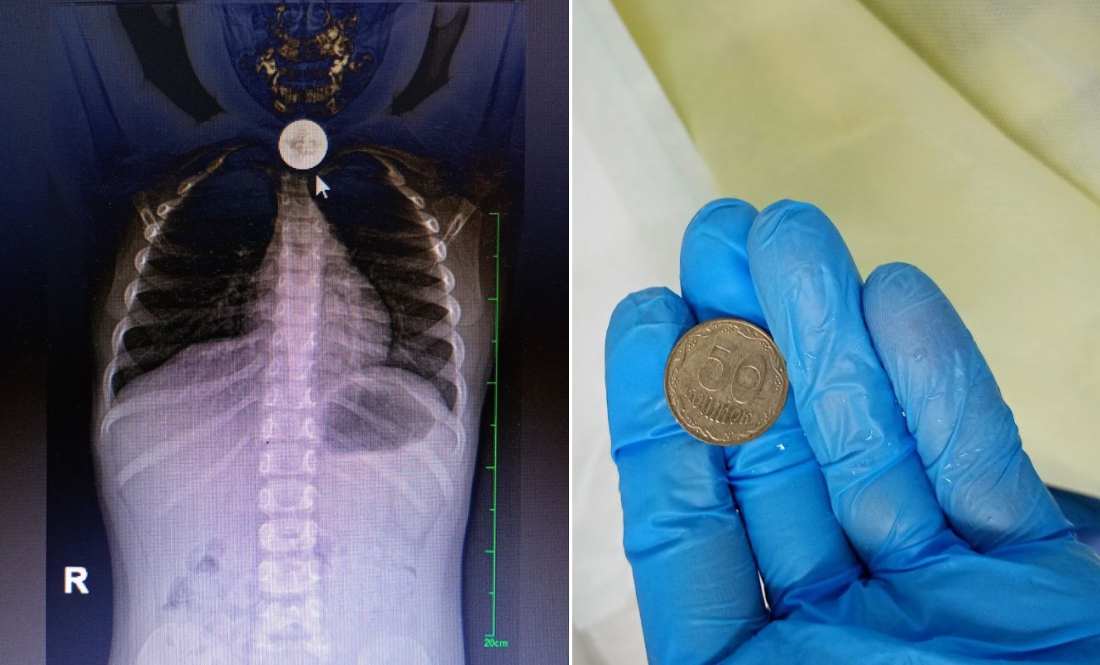

Він зазначив: на монетку в 50 копійок натрапили під час рентгенографії органів грудної клітки та черевної порожнини. Цьому передував візит до лікаря стривожених батьків.

До потрапляння в лікарню дитина гралася з монетою та ковтнула її. Були позиви на блювоту, слинотеча.

Стороннє тіло фахівці видалили ендоскопічно.